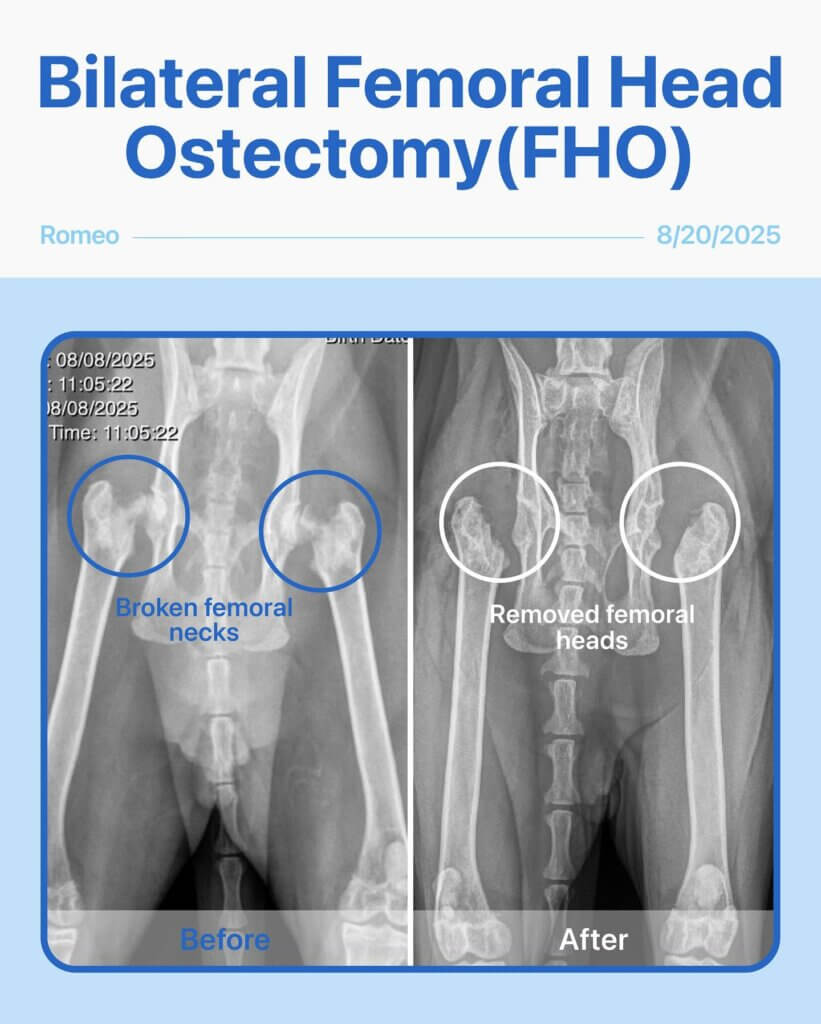

Romeo, our courageous 2-year-old male cat, came in with both femoral necks broken, making every step painful. He underwent bilateral FHO (Femoral Head Ostectomy) surgery to relieve his pain and help him regain mobility.

The surgery went smoothly, and Romeo is now on the road to recovery! The X-ray shows both femoral necks before surgery and the successful outcome after bilateral FHO. We’re so proud of his bravery!